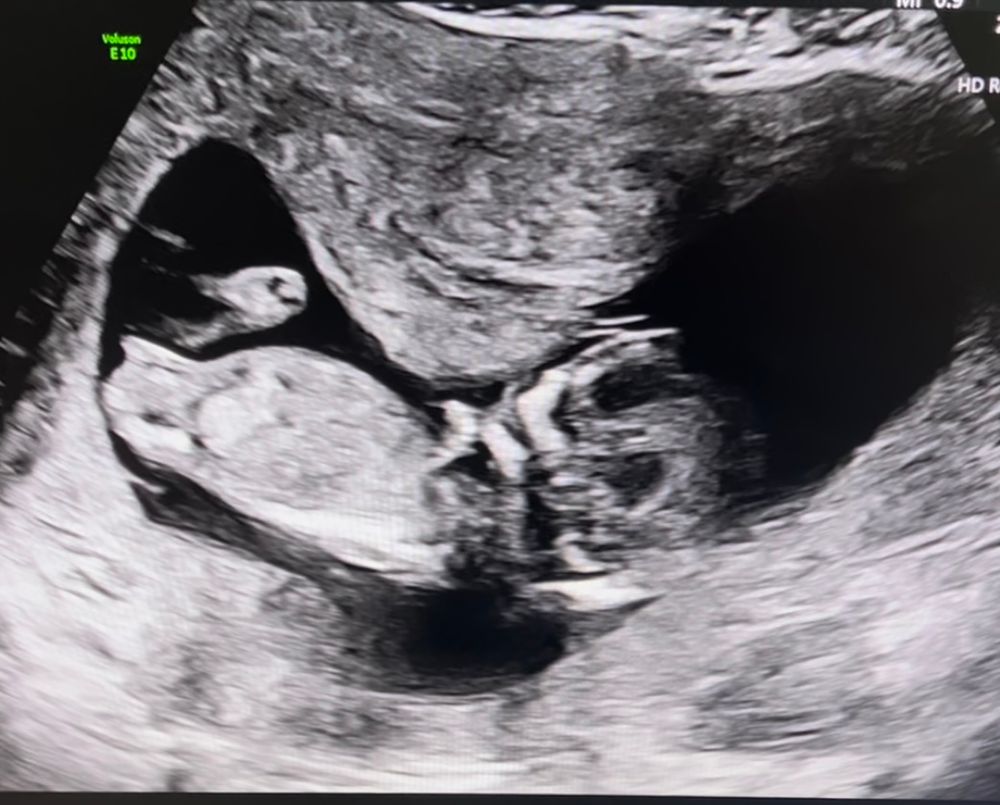

Девочки если я правильно понимаю это половой бугорок , на кого похож ребёнок, мальчик или девочка? Узистка даже предполагать не стала, говорит попозже приходить. И внешне и по половому бугорку. Хотя может это пуповина вообще 😅

У меня так же выглядел, но на самом кончике как бы бугорок был плавный переход такой, и врач сказал мальчик . Хотя по картинке из инета девочка, я видела такую же . Но врачу виднее🤭

Поздравляю с пройденным скринингом! Мне на 12 неделях предположила узистка мальчика, так и получилось. Подождите пару недель, там виднее будет. А на втором скрининге уже сами все увидите, если мальчик, то крупным планом))))